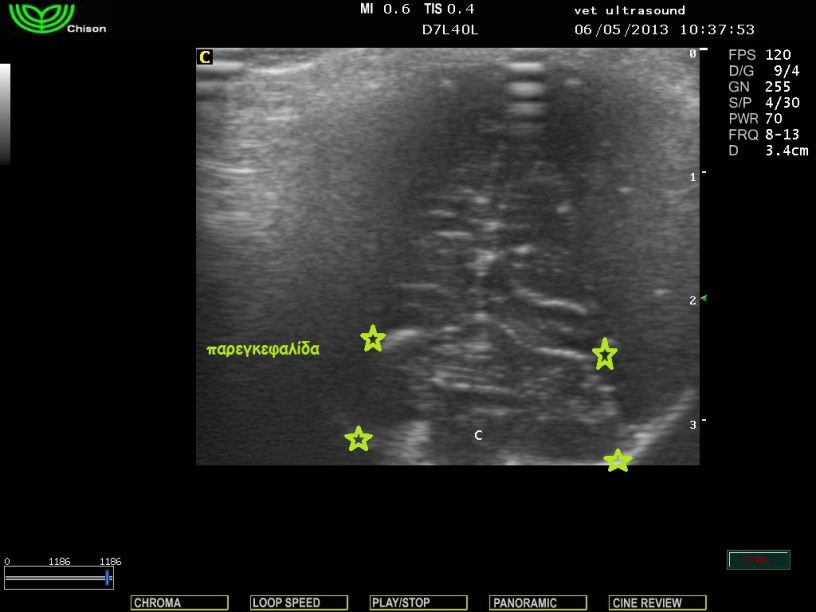

Στην κλινική εξέταση δεν παρατηρήθηκαν αλλοιώσεις στην νευρολογική εξέταση των εγκεφαλικών συζυγιών και των νωτιαίων νεύρων. Υπήρχε μία μικρή απόκλιση των οφθαλμών από τον κεντρικό άξονα και για τον λόγο αυτό είχε θορυβηθεί ο ιδιοκτήτης. Δεν είχε επέλθει οστεοποίηση των συναρθρώσεων των οστών του κρανίου, οπότε η υπερηχοτομογραφική εξέταση ήταν εφικτή διαμέσου της συνάρθρωσης των βρεγματικών με τα μετωπιαία οστά. Δεν υπήρχε διάταση των πλάγιων κοιλιών του εγκεφάλου και έτσι το ενδεχόμενο του υδροκέφαλου αποκλείστηκε.

Εγκάρσια τομή με φορά της δέσμης του υπερήχου προς το ινιακό τρήμα.